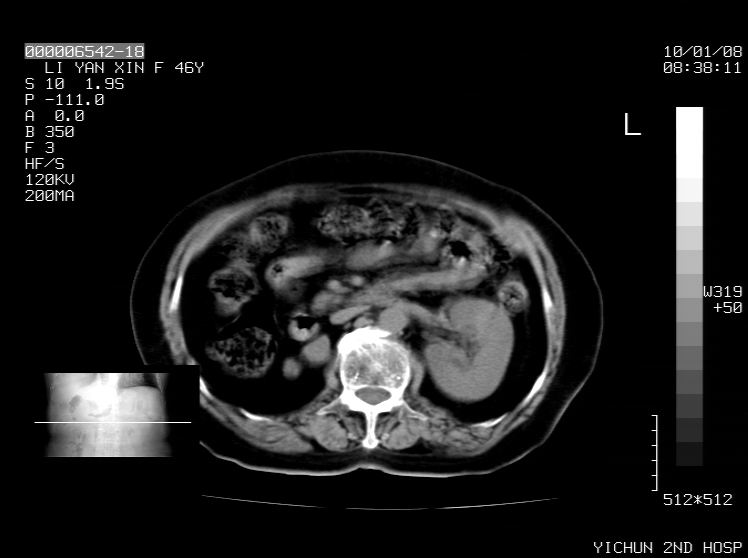

标题: CT24039:请会诊,女70岁,彩超考虑胆囊结石 [打印本页]

标题: CT24039:请会诊,女70岁,彩超考虑胆囊结石

右侧膈膨升,胆囊壁厚,右侧肾脏缺如。病史?

右侧膈膨升,右肾脏切除术后

右侧膈膨升,肝内钙化灶,胆囊壁厚,右侧肾脏缺如。病史?

右膈膨出,肝脏变异,肝内钙化,右肾缺如,脾大。

右侧膈膨升,肝内胆管结石?

右侧肾脏缺如。病史?

右侧膈膨升,胆囊壁厚,右侧肾脏缺如,增强,腔静脉旁是否是移位肾

肝脏变异致膈升高,肝左叶肝内胆管结石.右肾萎缩,左肾代偿肥大.

胆囊ct未见确切异常,请结合b超。右侧肾窝未见确切肾脏影,右肾萎缩?异位?

右侧膈膨升,肝内钙化灶,胆囊壁厚,右肾萎缩或发育不良。